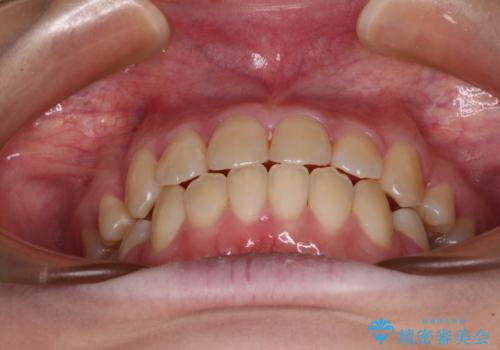

上下の出っ歯を治したい ワイヤー装置による抜歯矯正

- 上下前歯が前方に飛び出しているとのことで来院された患者様です。

上下左右第一小臼歯4本を抜歯して、積極的に口元を引っ込めるよう、ワイヤー装置にて矯正治療を行うこととしました。

口元の突出感は著しく改善され、横顔の印象が大きく変化しました。